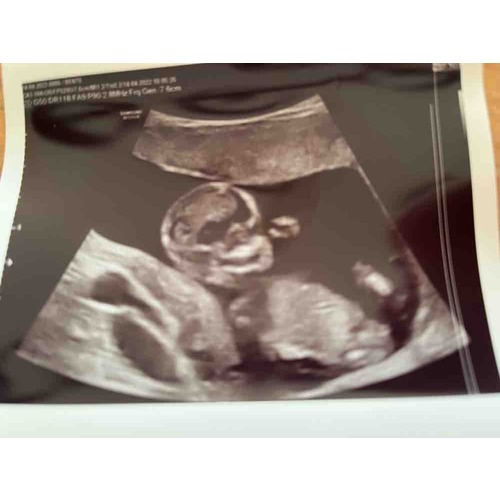

Ik heb hier een echo van 13.6 weken..Iemand die hier iets ziet!?

En foto nummer 2😅

Ik gok een meisje.

Nub is niet te zien voor mij, maar qua skull theorie denk ik een jongetje 😅